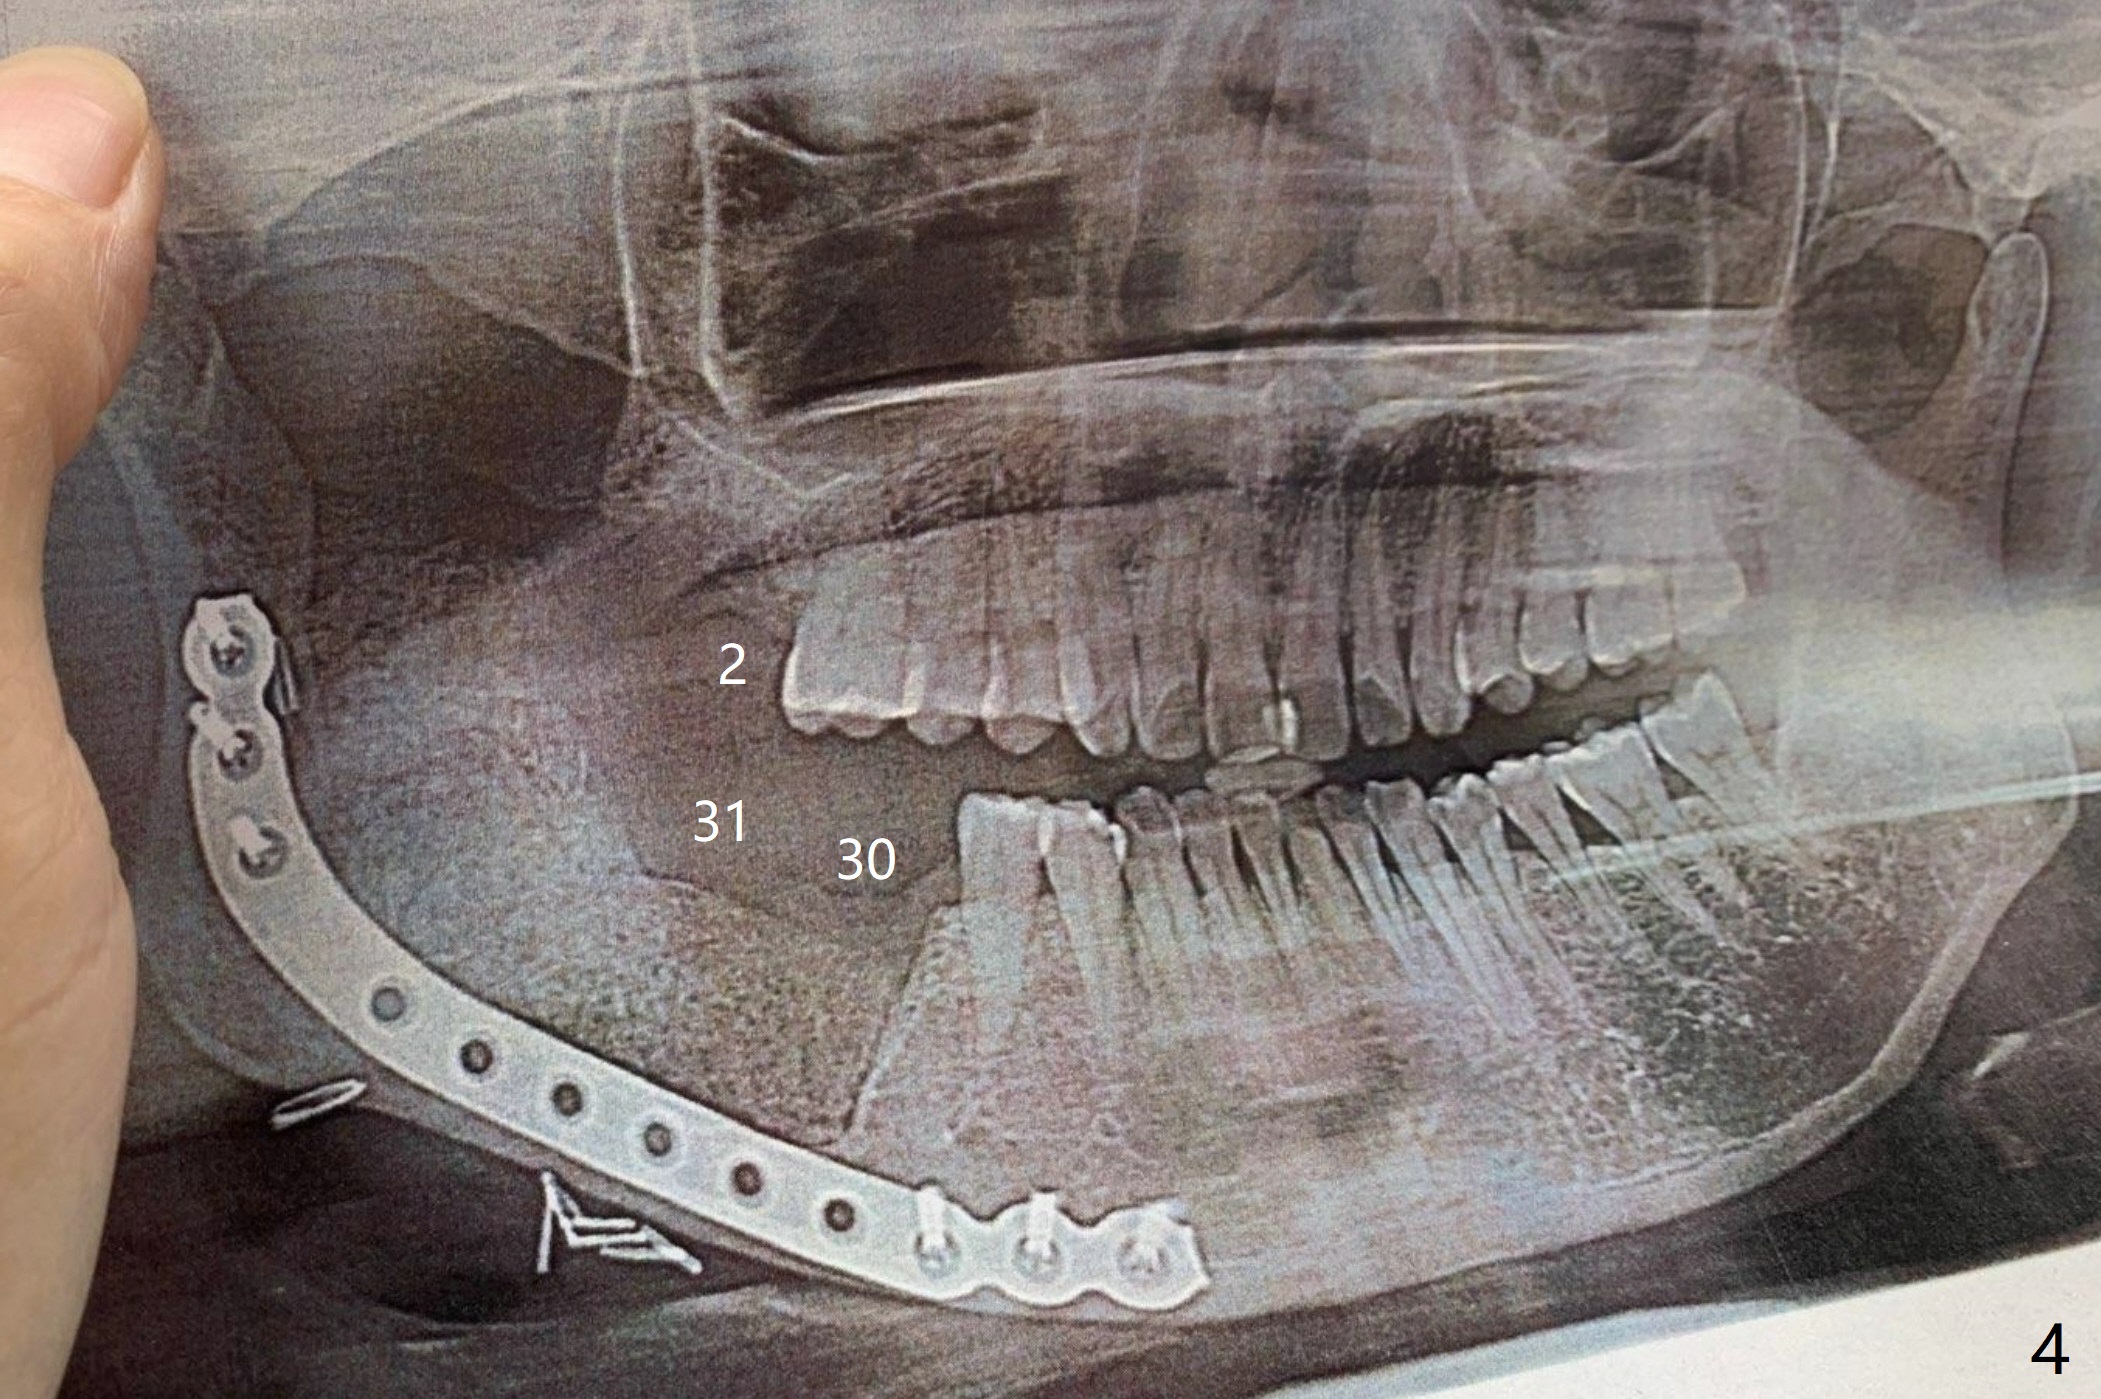

术前CT显示舌侧骨板吸收(图三)。术后全景片显示三个磨牙拔除,髂骨植骨,钢板固定(图四)。